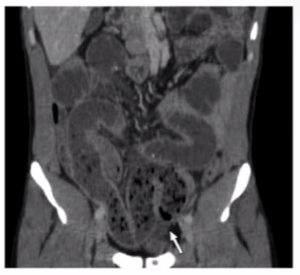

Etiology of this SBO?

The arrow showing a rapid transition point btwn dilated (proximal) and collapsed (distal) bowel

-w/ no other etiology this is diagnostic for SBO 2/2 adhesion